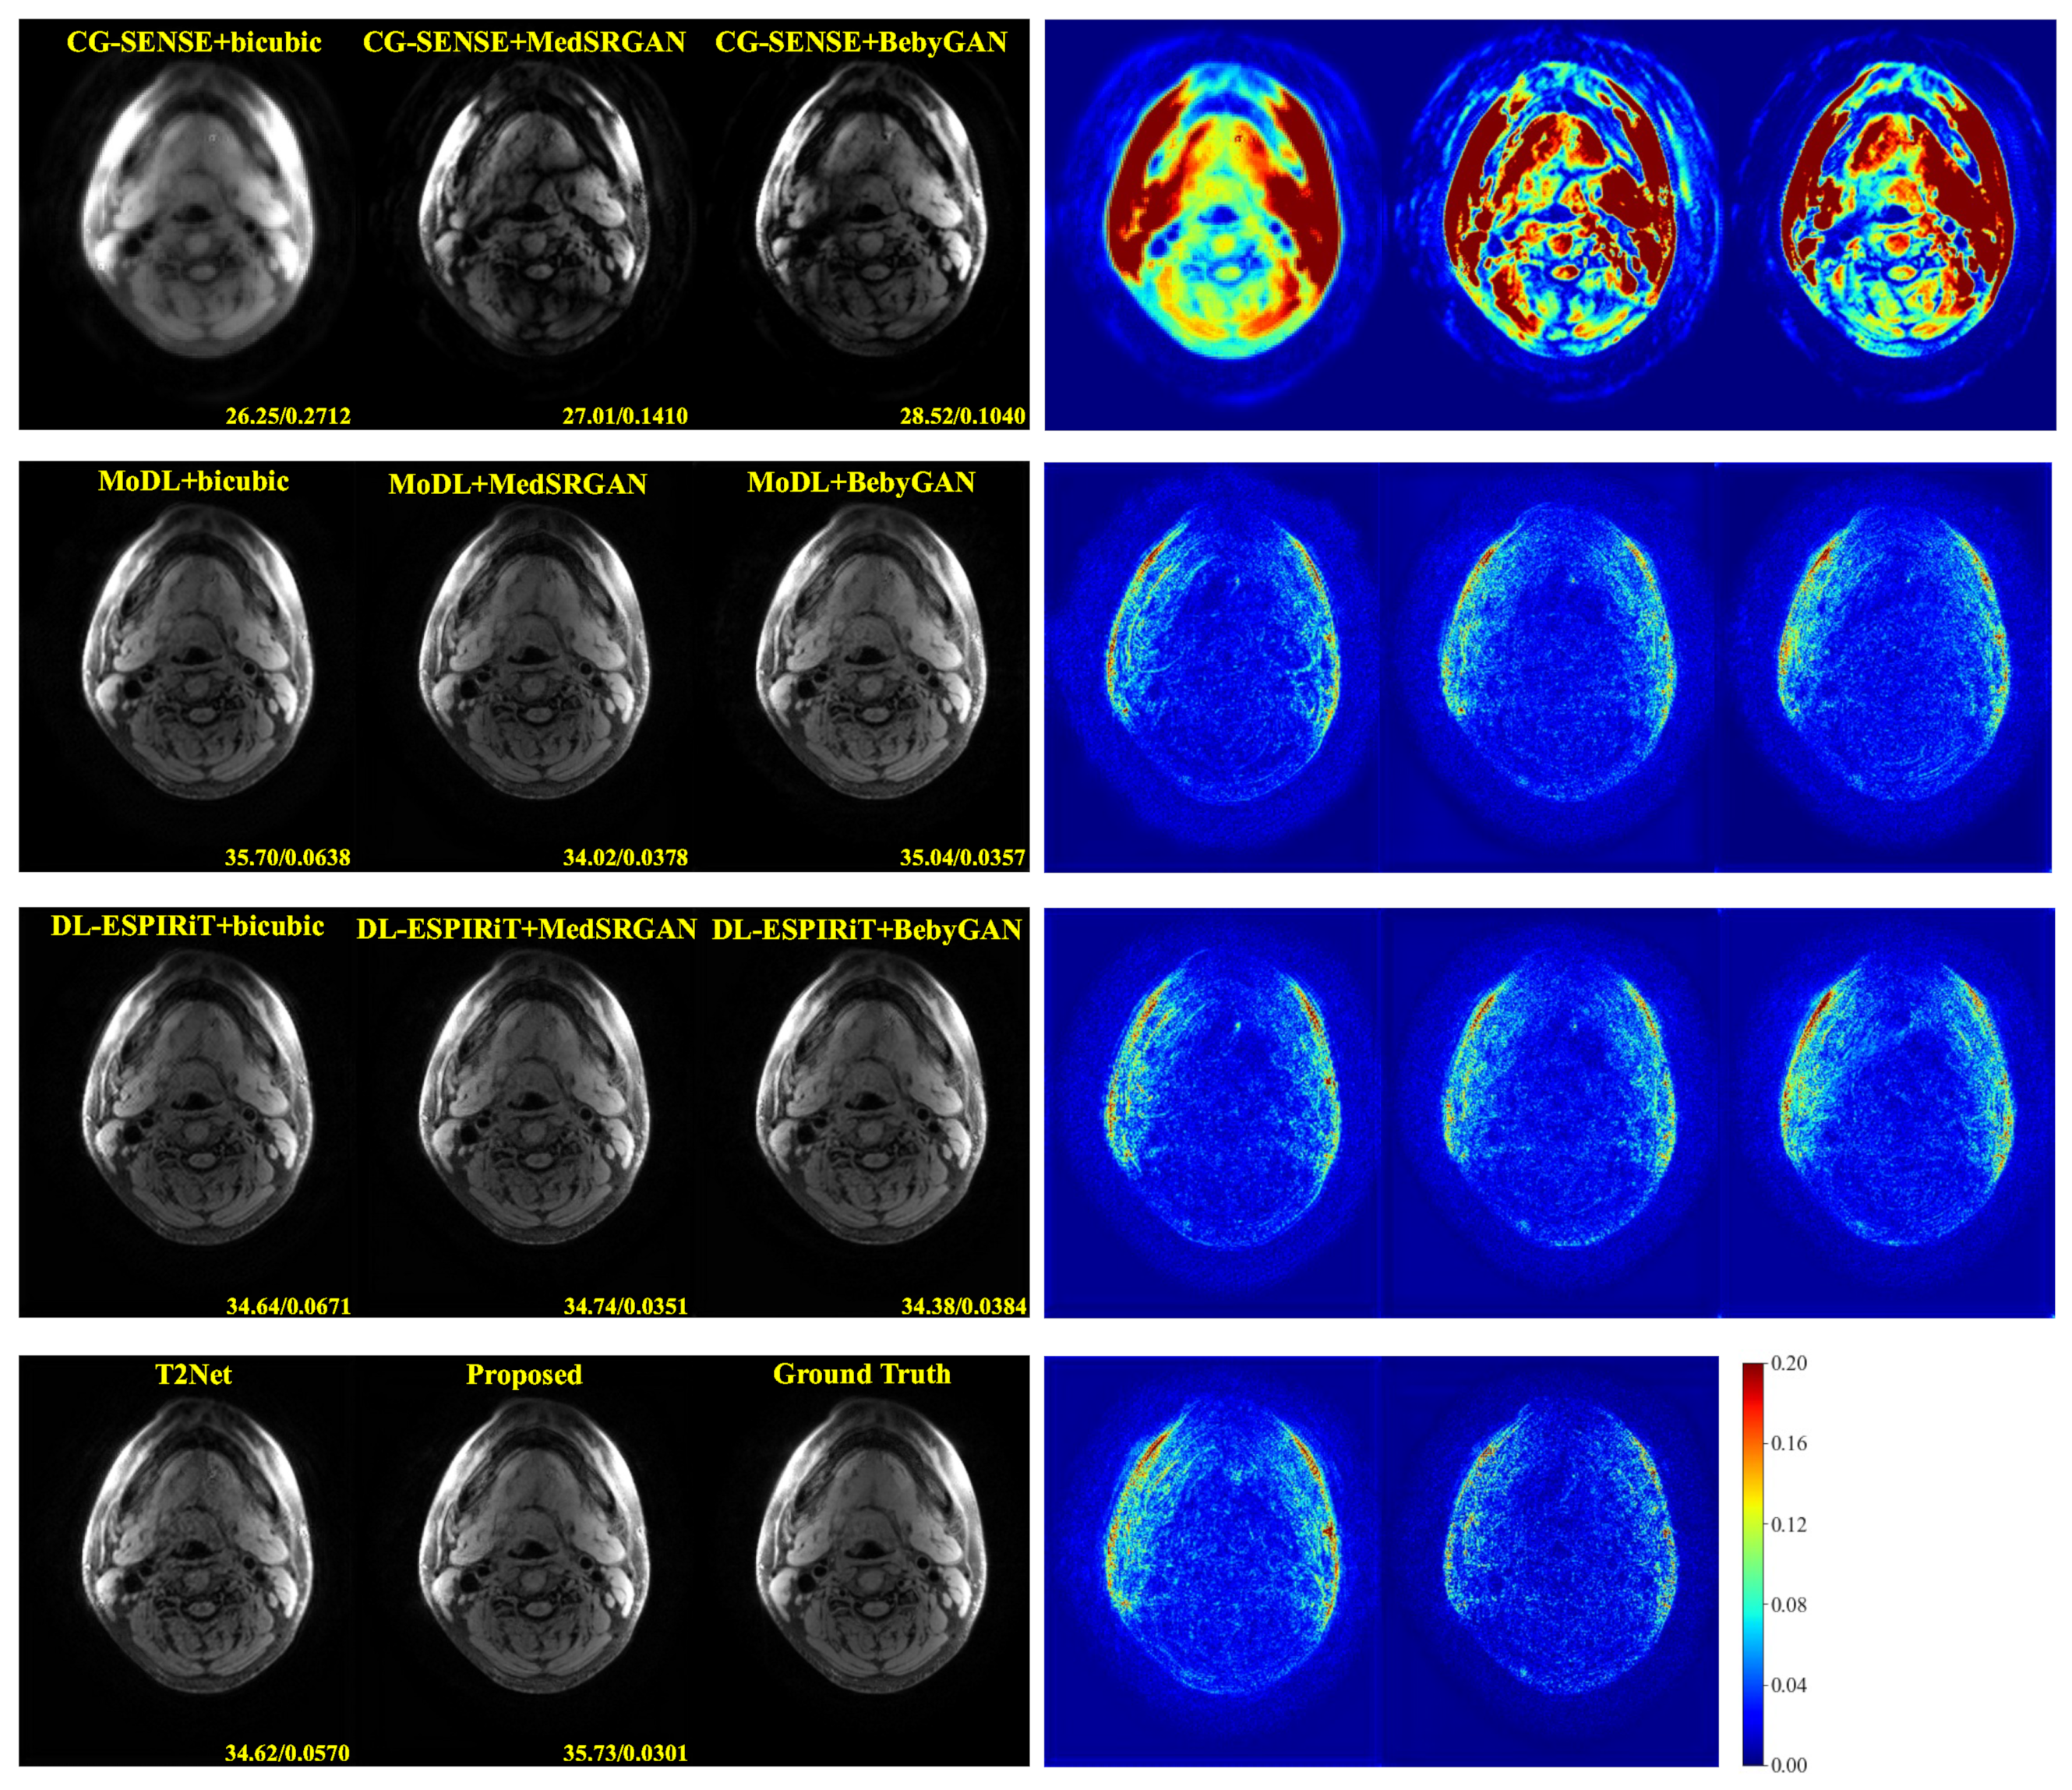

For a more intuitive comparison, we provide visual comparisons for each method. In Figure 5 and Figure 6, we illustrate the axial and sagittal views of the 2D brain dataset, respectively. In Figure 7 and Figure 8, we display the brain image and neck image of the 3D VWI dataset. For each method, we show the restorations along with the corresponding error maps. The images are placed on the left, the error maps on the right, and the PSNR and LPIPS metrics of each image are shown at the bottom right corner. From the error maps, it is evident that our proposed method consistently produces high-quality results with improved visual fidelity and better retention of structural information compared to the other methods.

Figure 5. Visual comparison of each method for a slice of axial view in the brain dataset.

Bioengineering 10 01107 g005